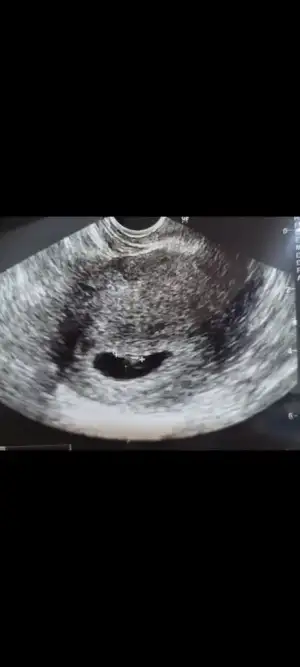

Çok teşekkür ederim.🥰 Eller kollar hareketlenmiş bir de. Öyle görünce içim kıpır kıpır oldu.Bir kızım var bir de oğlum olsun isterim.Ama kız olursa da cok mutlu olurum.Gercekten hiç fark etmez. Evlat sonuçta Rabbim hayırlısı neyse sağlıklı bir şekilde onu nasip eder inşallah.Kızıma hamileyken rüyamda kız olacağını görmüştüm.Bunda bebek gördüm ama cinsiyetini görmedim.@lolaylty 6+1 ve 7+1 ultrason görüntüsüne göre erkek demişti siz de kız dediniz.Hangisi olacak bakalım 😄 Hayırlısı olsun.Rabbim sizin bebeğinizi de gönlünüze göre sağlıklı bir sekilde kucağınıza almayı nasip eder inşallah.🙏💞

6+1 ve 7+1 i de görmek isterim kaçıncı sayfada hatırlıyor musunuz?